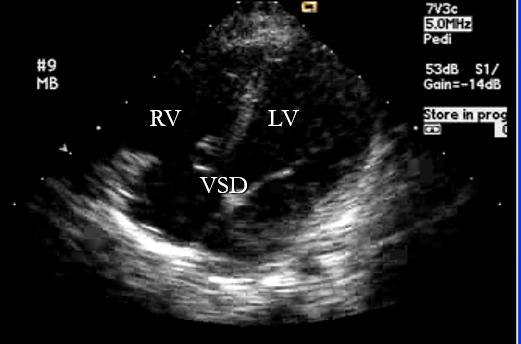

”孩子前几次得病的时候诊所里的大夫有和您说过什么吗?“大夫询问道。”没有啊,就说孩子肺部有许多罗音,肺部感染挺重的。“宝妈有些茫然。大夫正色道:”孩子心脏有些问题,需要做个彩超确诊一下。“宝妈顿时接受不了,”孩子心脏有问题?怎么可能呢?我们家里面没有谁有心脏病啊。“大夫解释道:”宝宝现在患的病是先天性心脏病最常见的一种,叫做室间隔缺损。孩子的左右心室之间出现了一块缺损,用通俗易懂的话来说就是多了个心眼。“宝妈呆住了。听大夫这么说,心眼多貌似不是个好事情啊。

宝妈有些焦虑了,难道孩子出现嘴唇发紫的情况是什么综合症么?孩子该怎么办呢?大夫说到:“彩色B超可以明确孩子室间隔缺损的部位、大小,甚至可以通过多普勒技术无创性的评估肺动脉的压力如何,为临床的治疗做出科学的评估。”宝妈忧心忡忡地问道:“心脏病是不是都要做手术啊?手术费用肯定很贵吧,我们家可担负不起啊。”大夫安慰道:“室间隔缺损是先天性心脏病中最常见的类型,占到了总数的20%~25%,根据解剖部位的不同分为膜周部缺损、双动脉瓣下缺损、流入部缺损和肌部缺损。有四成的室间隔缺损可以在孩子3~4岁时自然闭合,其中小型的室间隔缺损、膜周部和肌部的缺损容易自然关闭。如果孩子在婴儿期未及时发现,没有引起重视,感染后较容易出现心力衰竭促使艾森曼格综合症提前出现。当艾森曼格综合症发生时,再做手术的意义就不大了。因此,当务之急是评估孩子的先天性心脏病类型,判断孩子是否具备手术指证。如果需要手术治疗,我们不能耽误他。如果是因为经济的原因,国家现在有不少的基金对孩子心脏手术有资金支持,不会花很多钱的,您先去做检查吧。”

超声可以确诊孩子的先天性心脏病,由于其准确可靠又无创,值得推广

值得庆幸的是,孩子的分流量并不大,缺损直径大小为4mm,属于小型室缺。当室间隔缺损直径小于5mm时,心室水平的左向右分流量少,血液动力学变化不大。注意平时的护理和加强营养,孩子室间隔缺损自然闭合的可能性很大。但是当孩子的室间隔缺损大于5mm时,孩子的肺循环血流量可以达到甚至超过体循环血流量的1.5倍。正常情况下肺循环血流量与体循环血流量比值约等于1.当肺循环血流量大于1.5时即机体存在中等量的左向右分流,大于2时存在大量的左向右分流。当出现这样情况时,孩子是需要积极处理的,可以使用心导管介入治疗。这个孩子由于缺损部位直径较小,经过积极的抗感染治疗后,孩子的发绀症状明显缓解。但是室间隔缺损的孩子极易出现呼吸道感染后病情迅速加重,因此家长们在对存在先天性心脏病的孩子护理时需要更加谨慎小心,尽量避免孩子感冒。如果孩子存在发育迟缓、频繁的出现呼吸道感染、甚至有时出现唇周发绀的情况时,及时的就医排除先天性心脏病是很有必要的。祝宝宝们健康成长。